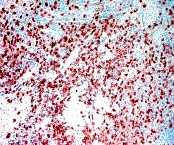

CD8 Antibody (603-060) in IHC (P)

Positive control: Spleen

Cellular location: Cell membrane.